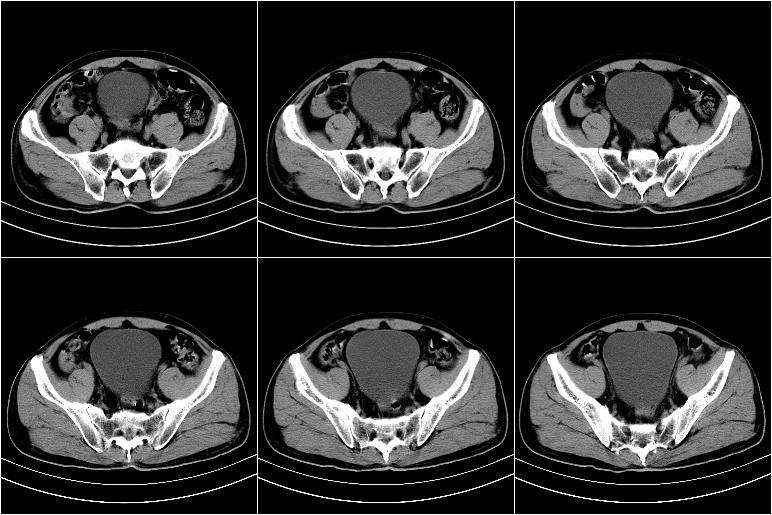

标题: CT21569:M,54Y,右侧中腹部疼痛,IVP示右侧输尿管中下段充盈缺 [打印本页]

标题: CT21569:M,54Y,右侧中腹部疼痛,IVP示右侧输尿管中下段充盈缺

右输尿管下段扩张积水。左下腹部肠管间质瘤不除外。

右侧输尿管扩张积水,考虑结石,最好做个增强除外输尿管占位性病变

右输尿管下段扩张

右侧输尿管扩张积水,最好做个增强除外输尿管占位性病变

支持右侧输尿管中下段扩张积水,建议增强排除占位。

ct21569和ct21569b(增强)结果:阑尾腺癌,侵犯回盲部及输尿管中段。手术切除部分升结肠、回肠及受侵4cm之输尿管,做回-横结吻合,输尿管支架置放术并吻合,术后病理腺癌,阑尾来源可能性大。